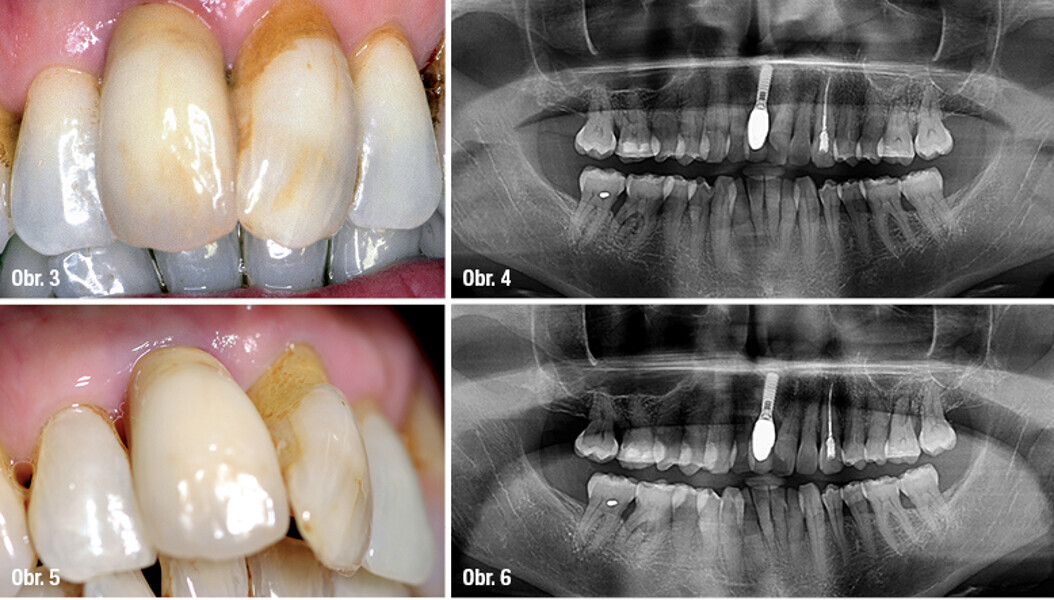

Triumfy a tragédie v implantologii